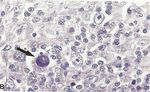

Figure 4 : lymphome de Hodgkin.

A : lymphome de Hodgkin : Plages de lymphocytes et d’histiocytes

avec des cellules de Reed Sternberg mononuclées et binuclées

(flèche) [25].

B : lymphome de Hodgkin : Une cellule de Hodgkin nécrosée

(flèche) avec 4 cellules de Hodgkin vivantes [25].